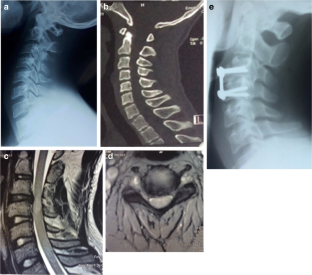

Fig. 1

Patients with cervical spine injury (413) were retrospectively reviewed. Six patients with neurological deficits were identified to have disc herniation without adjacent bone lesion. The diagnosis was confirmed by MRI. The Japanese Orthopedic Association (JOA) score was used to assess the severity of clinical symptoms. Different grading systems have been used in analyzing various stages of herniated cervical discs. All patients underwent anterior cervical decompression, insertion of autologous iliac crest graft, and fixation with cervical plate.

The causes of injury were road traffic accidents in four patients and sport and domestic accidents in one patient each. There were five patients with single intervertebral disc herniation and one patient with double. Pre-operative JOA score was 14 for three patients, the remaining three patients scored 10, 6, and 3 respectively. At final follow-up, the score was 17 for four patients and 14 for two patients.

Traumatic cervical disc herniation with neurologic deficit and without adjacent bone lesion is a rare condition. MRI is the golden examination to confirm diagnosis. Early recognition is essential for appropriate therapy and to minimize the extent of neurological deficit.

The MRI is mandatory in diagnosing different types of traumatic herniated cervical disc. Discectomy and anterior cervical interbody fusion using autologous iliac crest graft are the treatment options.